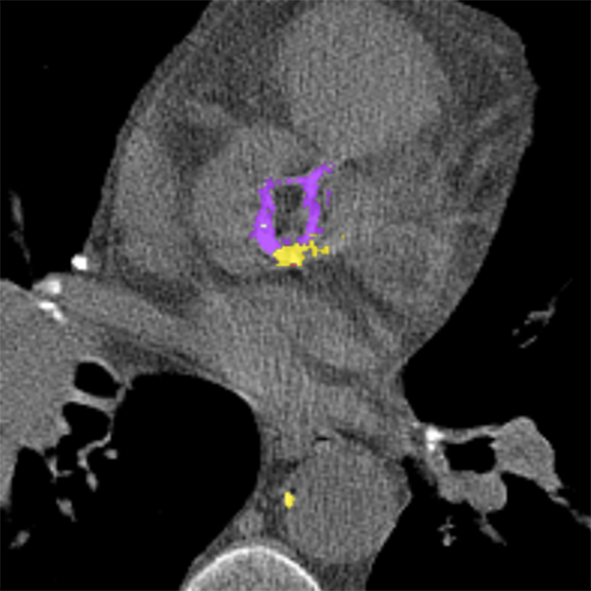

To establish a reference standard, calcifications were manually labeled in all scans. Scans were distributed among four trained observers and one radiologist with extensive experience in calcium scoring. To measure interobserver agreement, a subset of 100 scans (four scans from each of the 25 different scanner models and reconstruction algorithms) was annotated by two of the trained observers and the radiologist. Manual calcium annotation usually requires the observer to select only a single voxel per lesion. The lesion is then automatically segmented with region growing using the standard intensity threshold of . In low-dose scans, however, intensity based region growing often leads to large amounts of noise being segmented with the calcium (Figure 1). Moreover, it can lead to the spine and ribs being segmented together with calcium, or calcifications in arteries branching off the aorta being segmented together with calcium in the aorta. The observers therefore marked calcifications voxel-by-voxel () in the coronary arteries, the aorta and the aortic and mitral valves, including the annulus. Coronary calcifications were labeled as either left anterior descending artery (LAD), left circumflex artery (LCX) or right coronary artery (RCA). The left main coronary artery was considered part of LAD because these are difficult to distinguish on ungated scans. Motion artifacts caused by calcifications were annotated as calcifications because an exact separation of true calcification and artifact is often not possible. Depending on the amount of calcification and the image quality, the annotation effort varied from 5–10 minutes for images with soft reconstruction and little calcium to 60–90 minutes for images with sharp reconstruction and/or large amounts of calcium.

V-H Voxel-level vs. lesion-level annotation

The manual reference annotation was performed voxel-by-voxel to enable annotation of scans with poor image quality. To assess how much voxel-level annotation differs from the standard lesion-level annotation, we converted the voxel-level annotations into lesion-level annotations using 3D region growing with the standard calcium threshold (). Lesions were labeled using majority voting if they contained voxels with different labels. Scans with a more than five times increase in calcium volume were excluded. These were of the scans with soft reconstruction kernel and of the scans with sharp reconstruction kernel. In the remaining scans, the overall Agatston score increased on average by 85 in soft reconstructions and by 155 in sharp reconstructions. This clearly indicates that in low-dose CT scans, lesion-level annotation leads to an overestimation of the calcium score.